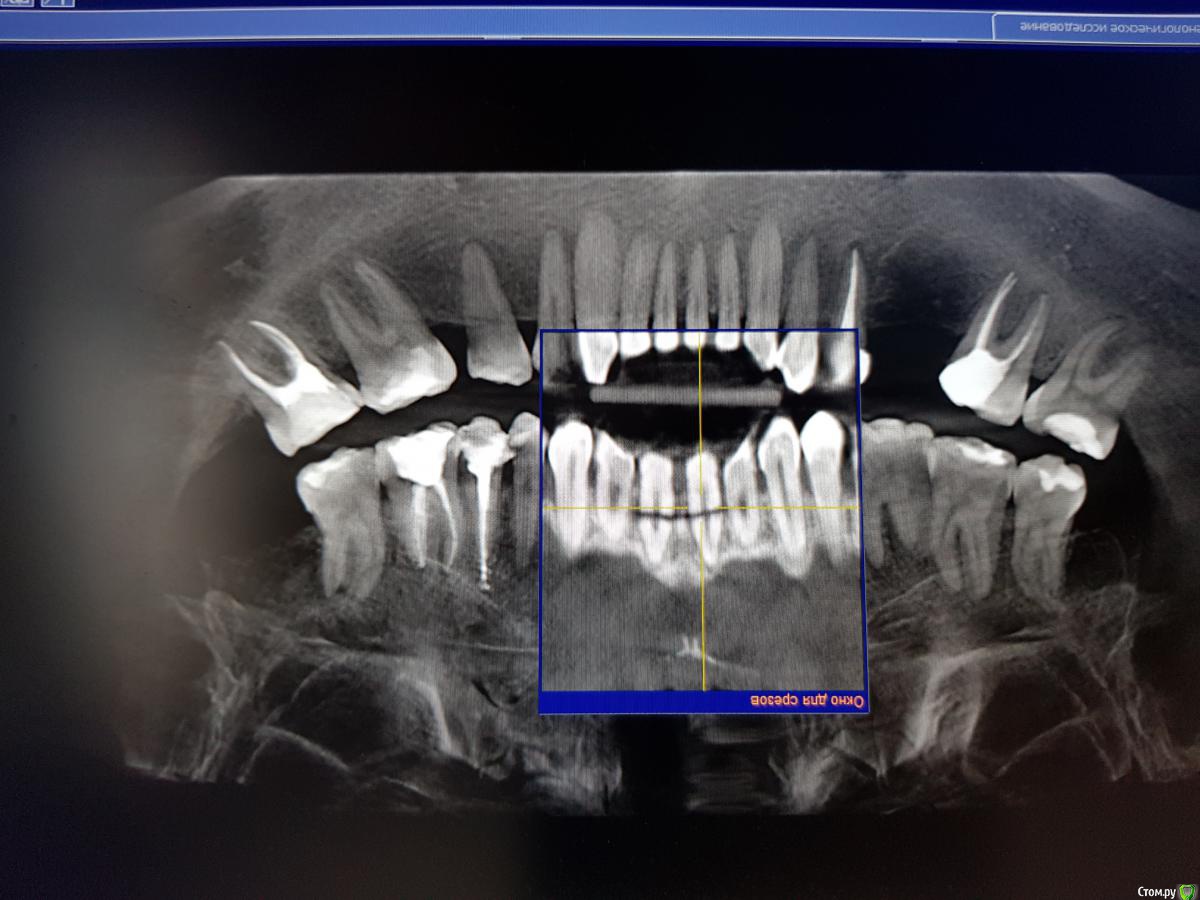

Kazankov.Egor Опубликовано 25 сентября, 2018 Поделиться Опубликовано 25 сентября, 2018 (изменено) Травма, фактура 11,21. Вопрос: одномоментно или отсроченно (НКР в момент удаления). Что смущает в одномоментной постановке:1) как заглубить имплантат, если использовать титановую сетку (поставить ниже уровня зенитов соседних зубов и край верхний край зафиксировать небно, т.е. фактически засыпать их наглухо или фиксировать мембрану от уровня платформы?)2) как это всё ушить правильно.3) те ли вопросы я задаю) Изменено 25 сентября, 2018 пользователем Kazankov.Egor Ссылка на комментарий

Дмитрий Л. Опубликовано 25 сентября, 2018 Поделиться Опубликовано 25 сентября, 2018 Вы видите перелом в.ч. между зубами? Если фрагмент сохранить не удастся, будут большие трудности с сосочком.Когда была травма? Какие жалобы? Status localis? Я за репозицию и шинирование. Ссылка на комментарий

Kazankov.Egor Опубликовано 25 сентября, 2018 Автор Поделиться Опубликовано 25 сентября, 2018 Когда была травма? Какие жалобы? Status localis? Я за репозицию и шинирование. Травма около месяца назад, зубы подвижны (1-2 степень), слизистая бледно-розового цвета, влажная, свищевой ход в области 11 зуба. Ссылка на комментарий